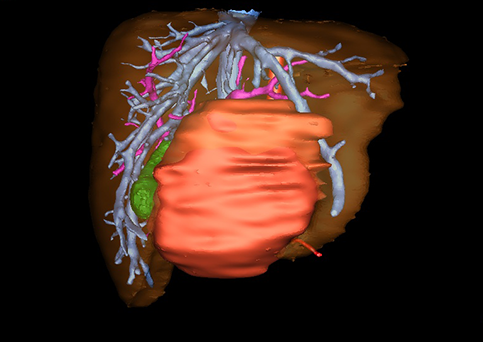

近年来由于数字医学的发展,基于可视化三维重建技术的计算机辅助手术系统极大推进了小儿肝脏肿瘤的精准手术的进步。可以立体透视肝脏解剖、精确掌握肝段的边界、精确测算肝段乃至任意血管所支配的功能体积、准确定位病灶及其与邻近血管的解剖关系,最终对不同手术方案进行比较、筛选和优化。因此,计算机辅助手术规划系统是实现精准肝切除的有力辅助工具,是未来数字外科、精准外科等21世纪外科新理念的重要技术支撑。

计算机辅助手术规划系统具有良好的操作可行性、计算准确性和三维显示效果,可半透明、交互式显示真实的肝内立体解剖关系和空间管道变异,准确计算肝内管道的直径、走行角度,两点间的垂直距离,和任意血管的支配或引流范围等传统二维影像无法获取的信息,有助于实施个体化手术,提高了手术的确定性、预见性和可控性。计算机辅助手术规划系统可直观显示预留肝脏的结构和功能,并可通过虚拟切割功能辅助术者对手术方案进行蹄选和优化,系统评估手术风险和制定对策,改变了部分二维规划的术式和切除范围,使部分二维规划认为不能切除的患者成功手术,提高了手术的根治性、安全性和病变的可切除性,更加符合精准肝脏外科的术前规划要求。详见第11章。

随着计算机技术及影像检查技术的不断发展,以精确的术前影像学和功能评估、精细的手术操作为核心的精准肝切除技术日益受到重视。基于数字医学的计算机辅助手术技术(computer-assisted surgery,CAS)则是实现肝脏精准手术操作的基础。计算机辅助手术系统(CAS)可将术前二维(two dimensional,2D)的CT/MRI影像数据进行三维(three dimensional,3D)重建,建立个体化的肝脏三维解剖模型,清晰显示肝脏内脉管系统的走行及解剖关系,还原病灶与其周围脉管结构的立体解剖构象,准确地对病变进行定位、定性和评估,制定合理、定量的手术方案,实施个体化的肝脏血管取舍分配方案及实施精准肝脏手术。一般认为CAS包括:创建虚拟的患者的图像;患者图像的分析与深度处理;诊断、手术前规划、手术步骤的模拟;术中实时导航。应用本技术后,由于可以更清晰地看出肿瘤的界限,特别是根据肝血管的显影,判断出肿瘤与门静脉及肝静脉的关系以在手术前较准确地估计出手术成功切除的可行性。以往部分根据普通强化CT判断无法手术的病例而被评估为可以成功切除并手术成功。